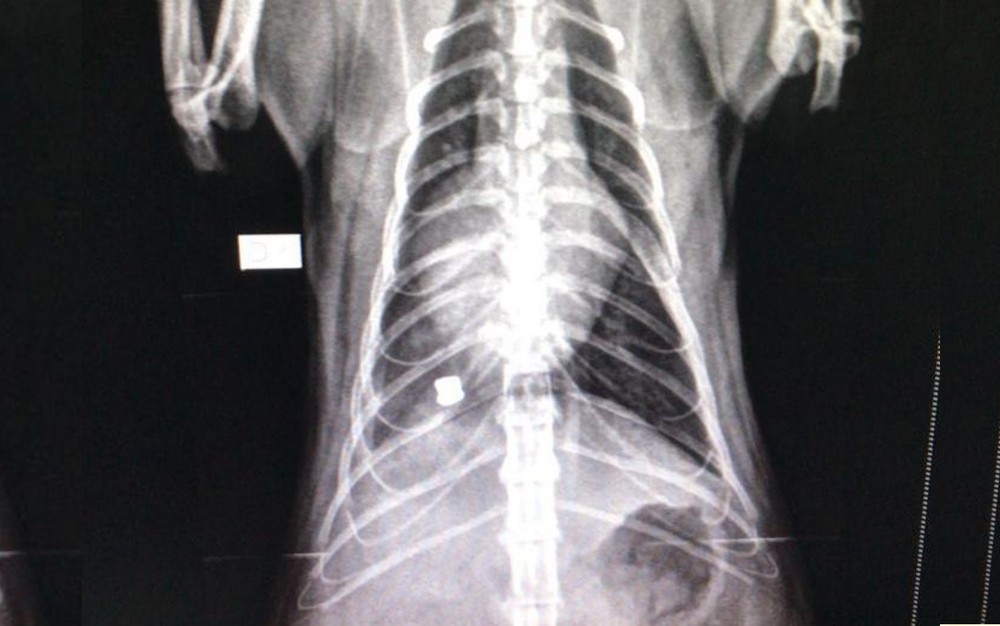

Segundo a estudante, ela e a mãe levaram o felino para o veterinário, onde descobriu o ferimento por chumbinho, após a realização de exames. Ainda segundo a estudante, a bala perfurou o pulmão do animal e precisa ser retirada. No entanto, é necessário que o quadro clínico do gato seja estabilizado para que possa ser operado.